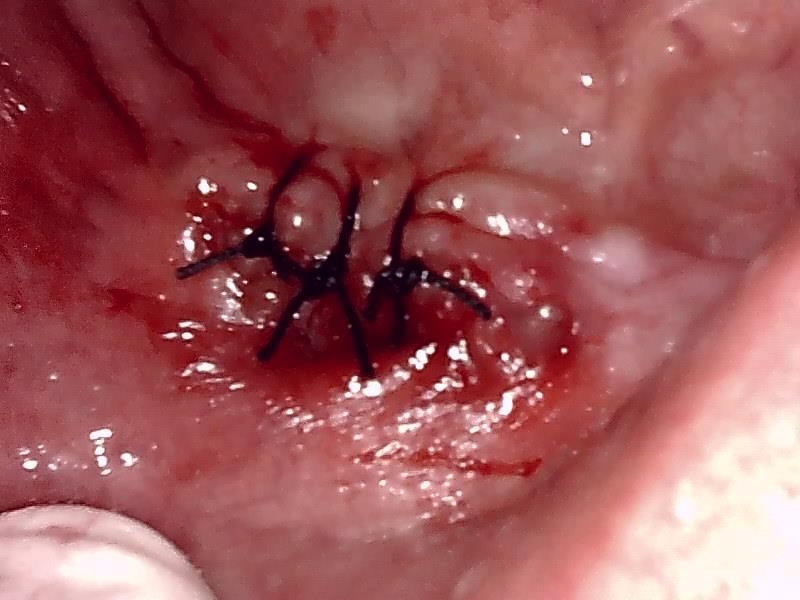

術前の顎堤の状態です。(上顎)

顎堤部の骨粗造面を整形して自家骨の骨移植を行い骨造成した。

縫合した状態です。